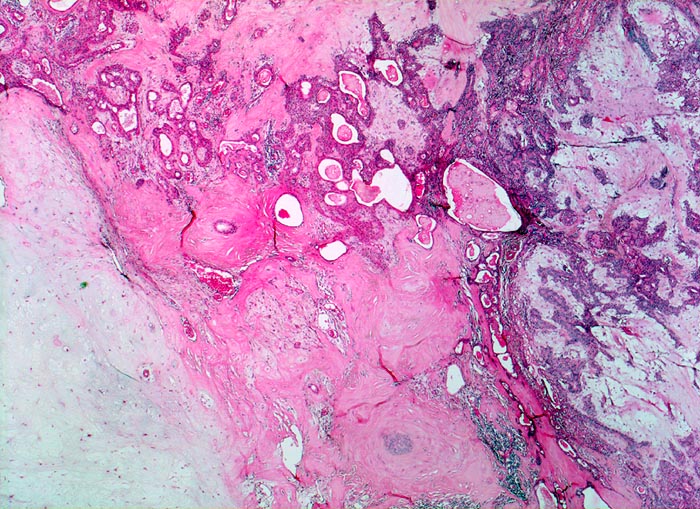

PathoPic – image database / PathoPic ID 3423 - Pleomorphes Adenom der Speicheldrüse

Pleomorphes Adenom der Speicheldrüse

In dieser Übersichtsaufnahme kommt die Pleomorphie gut zur Darstellung. Innerhalb der unterschiedlich dichten Matrixkomponenten finden sich drüsenbildende epitheliale Komponenten.

5cm grosser bekapselter Tumor in der linken Parotis.